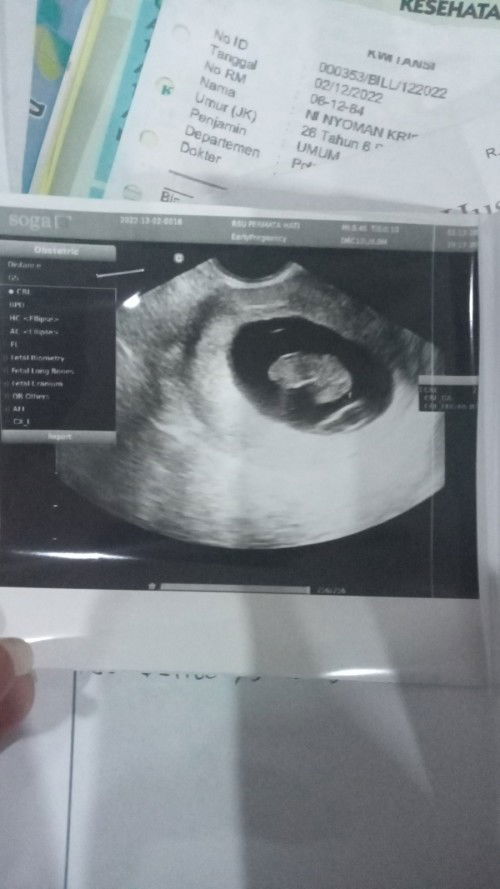

Mau sharing Bun Apa ada yg pake uvultes? Lalu ketika udah dapet masa suburnya tepat Hb di masa subur tapi gagal ada yg pernah ngalamin Bun? Soalnya aku kemarin pake ovultes sekali pake bener2 jadi.. Tp di bulan Desember kemarin bebyku dibilang sudah berhenti berkembang dan harus dikuret.. Mau coba ulang pake uvultes lagi Dan mau sharing juga sama bunda2 pejuang garis dua #seriusnanya #bantusharing #firstmom

Sharing dong bunda 2minggu lalu saya melakukan tindakan kuret karna beby10minggu berhenti berkembang

Kata dr ini karana kelainan genetik Biarpun dia mau berkembang kemungkinan besar si Beby lahirnya cacat ... Apa bunda ada yg ngalamin hal sama kaya saya? Kalo ada untuk selanjutnya kita perlu cek ke dr ga ya untuk mastiin aku atau suami yg kurang baik Atau boleh setelah tiga bulan ini langsu promil mandiri Atau lbih baik promil di Dr? Oh iya aku juga hamil pertama umur 2bulan ngalamin pendarahan sampai umur 7bulan.. Tp untuk anak pertama swaha lahir sehat cantik dan tidak kekurangan suatu apapun Bantu jawab ya Bunda2 #bantusharing #seriusnanya